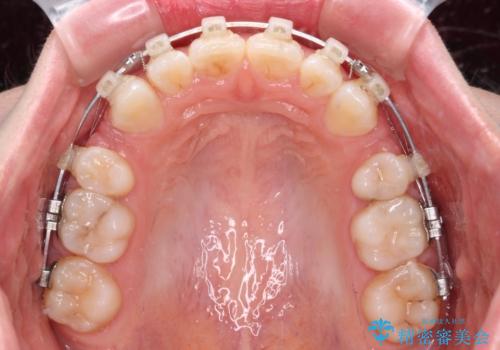

- 矯正装置

- クリアブラケット

- 前歯の出っ歯と口元の閉じにくさを気にして来院された患者様です。

口元を積極的に引っ込めるために、上下左右の小臼歯4本を抜歯することとしました。